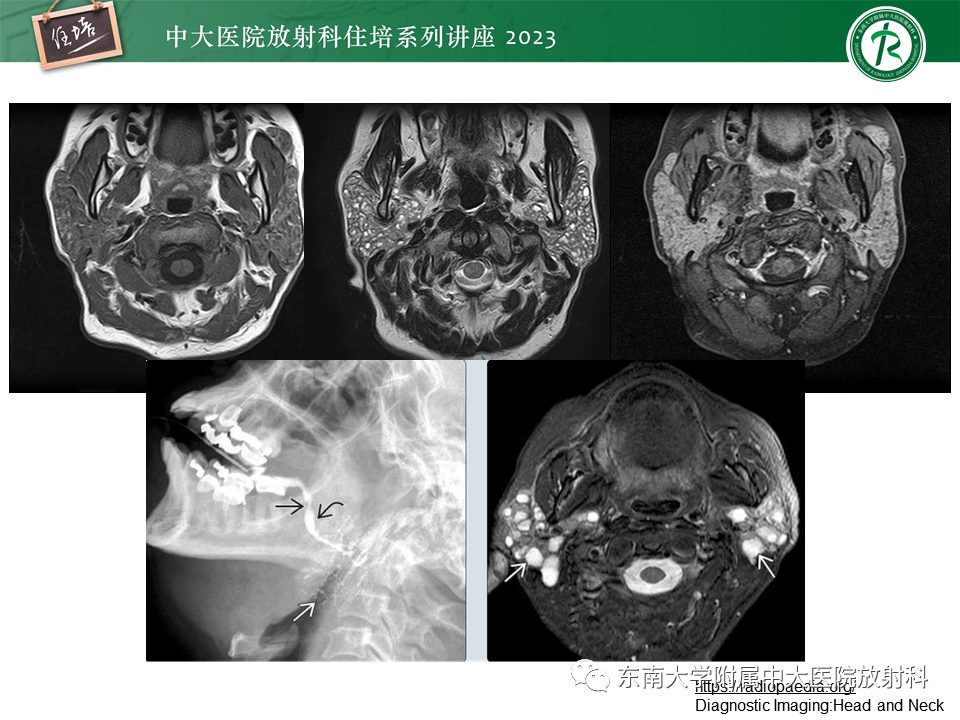

腮腺病变影像表现及诊断思路